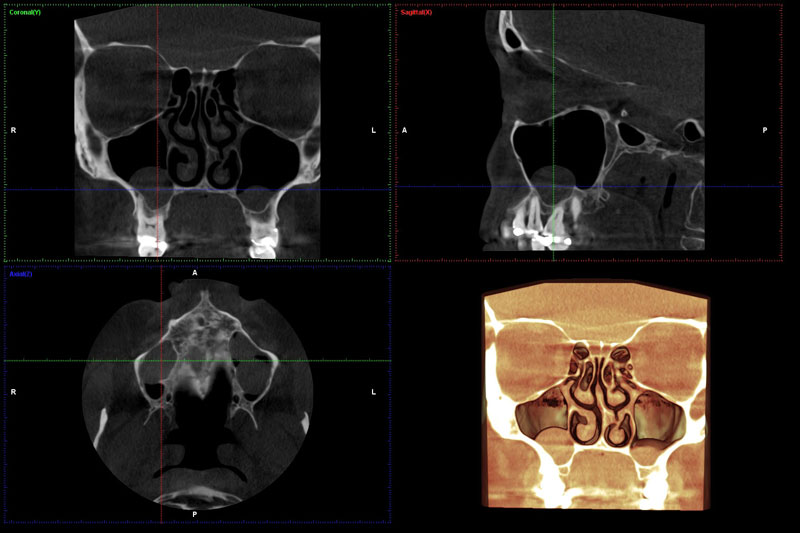

Programi za sinus, TMZ, cefalolometriju